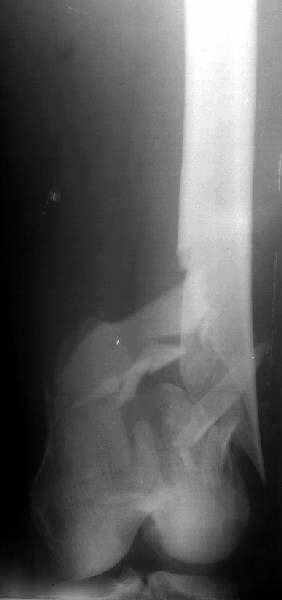

1

2

de> you think you are using antigrade nails for some very low

de> fractures including some intercondylar fractures.

Exactly. It seems the option looks underestimated.

de> Do ou have a reference supporting antigrade nailing in such

de> occasio in favour of other choices eg DCS, Supracondylar nail,

No, i haven't seen such comparisons. However some advantages of closed antegrade nailing vs conventional plating looks self-evident like no site opeining, no bone skeletization, less blood loss, no need for autografting... If you or other colleagues can help me with the references it would be greatly appreciated. I would be interested also to compare ante- vs retrograde nailing for the localization.

de> And perhaps you could show us also some of your results ,

de> that is (follow up) not immediate postop x rays.

I attached an example of C2 fracture with result of the same technique in 5 months.